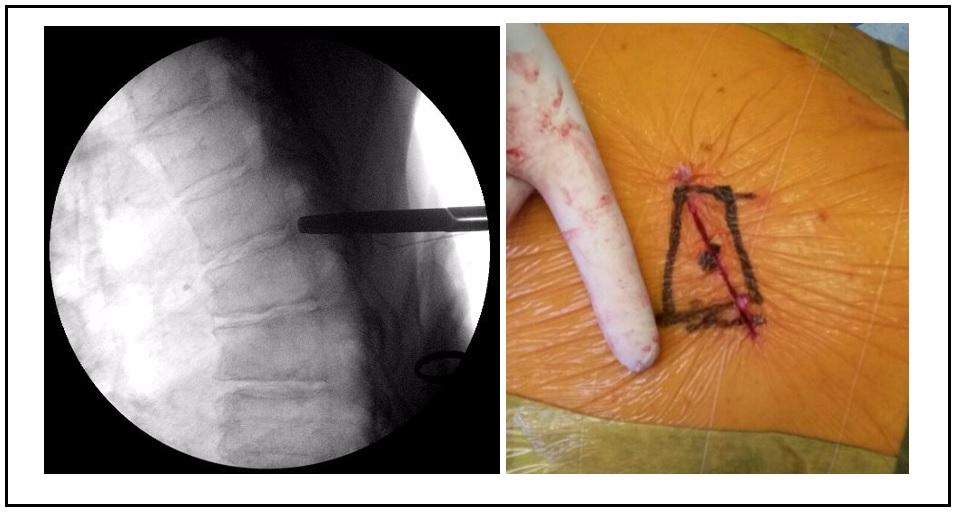

We present the case of a 64-year-old male with spinal compression symptoms, central disc herniation calcified at the fifth thoracic vertebra, which migrated to the lower end of the sixth thoracic vertebra. Diagnosis was clear for spinal cord compression. Partial posterior corpectomy of the sixth vertebra was performed with a minimally invasive transthoracic transpleural lateral approach and without additional fixation. The patient had a good outcome on follow-up, without progression of neurological symptoms or residual rib pain.